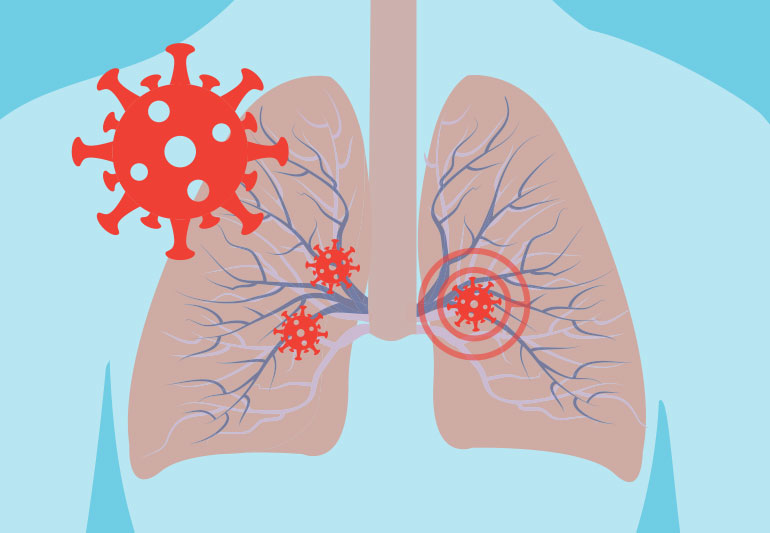

What Coronavirus Does to the Lungs

It is not news by now that the novel coronavirus, COVID-19, causes damage to the respiratory system. Questions like how and why, have a clearer understanding on the mechanisms in which the virus works than we did when the outbreak broke out earlier in the year.

The main types of respiratory damage caused by COVID-19 are pneumonia, ARDS, Sepsis, and superinfection;

Pneumonia – affects the lungs become filled with fluid and inflamed, leading to breathing difficulties. When cases become severe a ventilator is required when a patient must be intubated with a breathing apparatus. However, most people recover from pneumonia without any permanent lung damage, the pneumonia associated with COVID-19 may be severe. Even after the disease has passed, lung injury may result in breathing difficulties that might take months to improve according to Dr. Galiatsatos.

ARDS – The air sacs become filled with fluid leaking from the tiny blood vessels in the lungs which can create onset of shortness of breath. ARDS can be fatal. People who survive ARDS and recover from COVID-19 may have lasting pulmonary scarring.